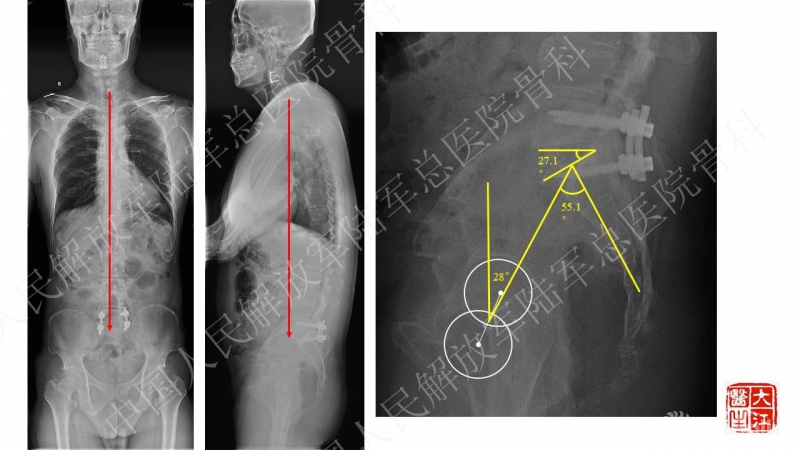

男性,67岁,主诉:车祸外伤后腰痛伴双下肢疼痛3月余。

3月前骑车被汽车撞倒,额面部着地,伤后出现双上肢剧烈疼痛,双上肢肌力减弱,以手内肌为主,活动受限,诊为“急性中央型颈脊髓损伤”,后全麻下行“颈前路颈3/4椎间盘切除椎间植骨融合术” 术后患者双上肢症状恢复良好,出院后离床活动即感腰痛剧烈,行走约100米感双下肢疼痛,疼痛主要位于双侧小腿后方,右侧为著,休息后可缓解,但体位改变疼痛加重

2013年曾因“腰椎管狭窄症”于外院行“腰椎减压、椎间植骨融合术”,术后大部分症状缓解,遗留部分右下肢麻木,效果满意

腰椎前屈后伸活动度受限,腰4/5及腰5骶1棘突水平叩痛,腰部后正中可见纵行12cm愈合手术切口瘢痕,胸10平面以下皮肤感觉减弱,右侧为著,右侧股四头肌、胫前肌、踇长伸肌IV级,双侧股神经牵拉试验阳性,直腿抬高试验双侧。双侧Hoffmann征、Babinski征阳性,腰部VAS8分,右下肢6分,左下肢4分

患者主诉为腰痛伴下肢疼痛,腰痛为主,翻身活动、下地时疼痛加重。体格检查也为下腰段的叩压痛,影像可见腰5-骶1断棒。断棒的原因都是力学应力相关的原因,而患者SVA(矢状位垂直轴)不大,全身平衡状态尚可。结合CT表现,应怀疑腰5-骶1节段未融合。

本病例的焦点在患者腰痛的原因,患者明确其腰痛非慢性腰痛,伤后出现。结合病史、体格检查、断棒的表现,主要考虑下腰段的原因。要考虑两个原因,一是腰5-骶1的未融合,断棒后不稳,局部应力集中。二是断棒后局部异常活动,带动瘢痕牵拉硬膜囊及神经根的向背侧牵拉,这种异常活动在残留小关节的抵挡下会引起严重卡压,而出现下肢的疼痛、甚至神经功能损害等。患者行原术区内固定取出,腰5-骶1内固定术,术后取得良好效果,证实患者本次疼痛病因为腰5-骶1节段断棒后应力集中、异常活动。

术后资料:

基于以上讨论结果,李放教授进行了总结:

患者疼痛为伤后出现,不是根性痛表现,而是机械性疼痛,活动及下地时明确。上位节段已融合,考虑到长节段固定后腰5-骶1节段由于杠杆原理出现内固定失败的风险大,术中取出原内固定后,仅行腰5-骶1短节段固定,取得了良好的临床效果。美中不足的是,因椎管内瘢痕粘连重,未重新加强融合,之后需严密随访。